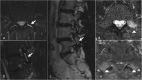

Low back pain (LBP) is the most common pain syndrome, and is an enormous burden and cost generator for society. Lumbar facet joints (FJ) constitute a common source of pain, accounting for 15-45% of LBP. Facet joint degenerative osteoarthritis is the most frequent form of facet joint pain. History and physical examination may suggest but not confirm facet joint syndrome. Although imaging (radiographs, MRI, CT, SPECT) for back pain syndrome is very commonly performed, there are no effective correlations between clinical symptoms and degenerative spinal changes. Diagnostic positive facet joint block can indicate facet joints as the source of chronic spinal pain. These patients may benefit from specific interventions to eliminate facet joint pain such as neurolysis, by radiofrequency or cryoablation. The purpose of this review is to describe the anatomy, epidemiology, clinical presentation, and radiologic findings of facet joint syndrome. Specific interventional facet joint management will also be described in detail. TEACHING POINTS: • Lumbar facet joints constitute a common source of pain accounting of 15-45%. • Facet arthrosis is the most frequent form of facet pathology. • There are no effective correlations between clinical symptoms, physical examination and degenerative spinal changes. • Diagnostic positive facet joint block can indicate facet joints as the source of pain. • After selection processing, patients may benefit from facet joint neurolysis, notably by radiofrequency or cryoablation.